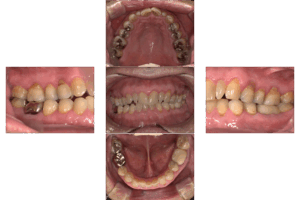

・口腔内写真の撮影

治療開始前のお口全体や個々の歯周ポケット周辺の炎症状態を写真で記録します。治療後の再評価の際に比較することで、客観的な改善度を把握でき、患者さんご自身も努力の成果を視覚的に実感できます。

※患者様の許可を得て記載しております。